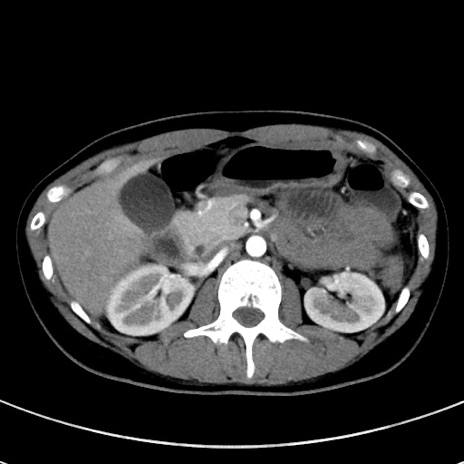

症例17(横断像)

【症例】20歳代女性

【主訴】嘔吐、下腹部痛

【現病歴】昨日夕食後に嘔吐し下腹部痛が出現。本日になっても嘔吐持続し改善しないため来院。

【身体所見】意識清明、BT 37.2℃、BP 108/67mmHg、腹部:平坦、やや硬、下腹部正中から右にかけて圧痛あり、反跳痛軽度あり、tapping pain(+)。

【データ】WBC 13600、CRP 14.94